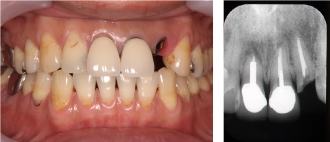

インプラント症例① ~歯を一本失った例~

●歯の頭の部分が取れてしまいました。

●虫歯も進んでおり、この歯は抜かないといけません。

保険治療では、両隣りの歯を削ってブリッジを入れないといけません。

●インプラントを1本入れました。

●こうする事によって、健康な歯を削らずに歯を入れる事ができます。